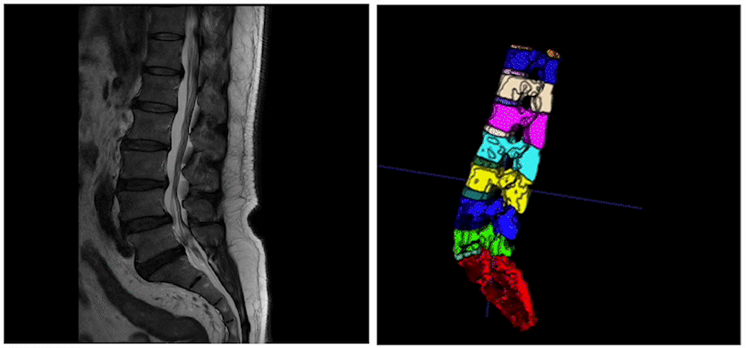

针对3D医疗分割场景,发布3D医疗影像分割方案MedicalSegV2。该方案支持3D交互式标注,实现高精度、定制化、全流程医疗影像分割。详情可参考:https://github.com/PaddlePaddle/PaddleSeg/tree/release/2.7/contrib/MedicalSeg

图4 3D医疗影像分割效果